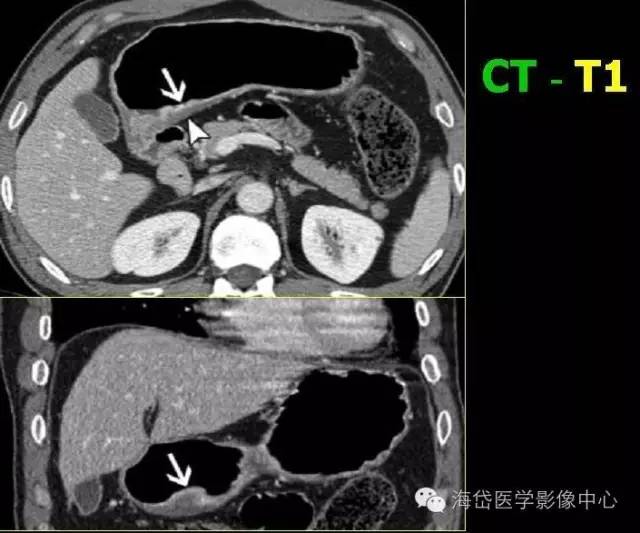

T1:低密度的粘膜層保持完整